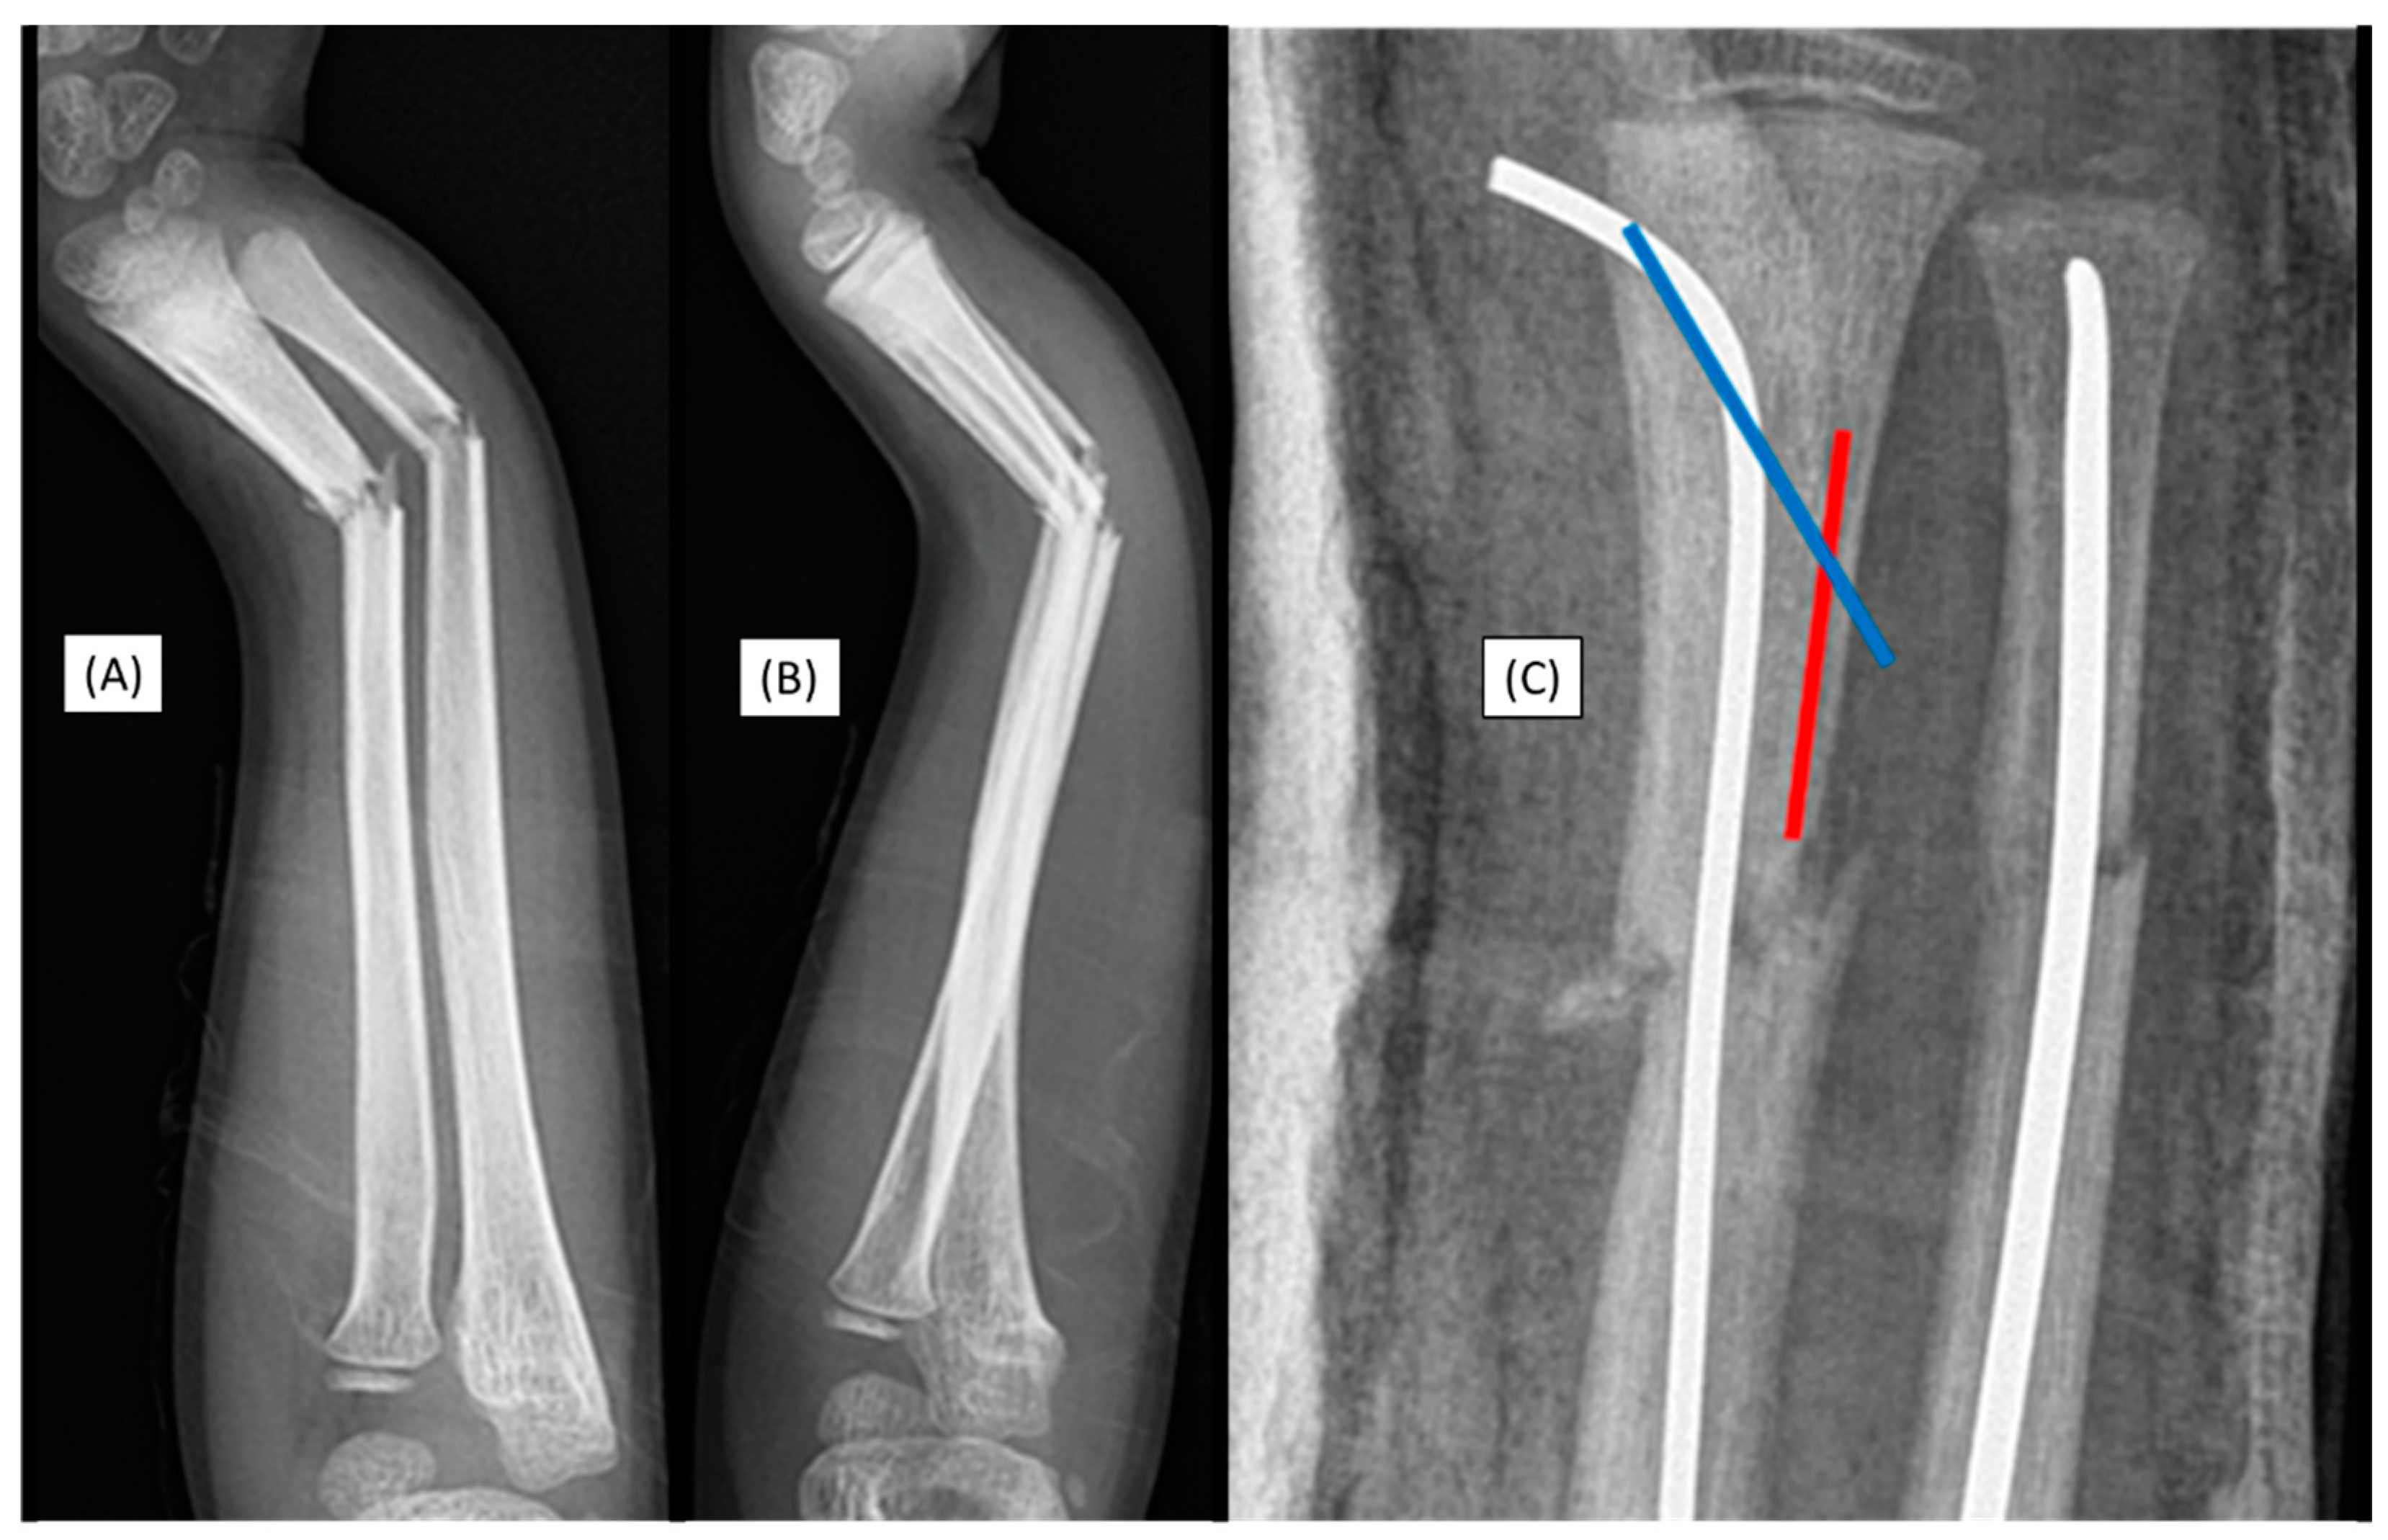

3.3. Case 3: Apical Implant Splitting

A 10-year-old child was injured while playing on a trampoline. He suffered a complete (22-D/4.1.) fracture of the right forearm. Following the closed reduction of a complete proximal third forearm fracture and proper preparation of the medullary cavity, the introduction of the (3.2 mm) absorbable IM PLGA implant at the fracture site was difficult (Figure 3(A-B)). The BIN could not be passed through the fracture gap, and the β-TCP marking was visible outside the bone's medullary cavity, projecting onto the interosseous membrane. After removal of the implant, we observed that the end of the nail had split (Figure 3(C)). This can be explained by challenges in surgical technique that led to an implant-related complication (implant failure) and due to the fact that after losing the precise reduction, the introduction of the absorbable implant was forced, causing it to break. Therefore gentle implant insertion in case of obstruction is preferred, like withdrawing and repeating the preparation of the medullary cavity with an appropriately sized dilator.

Figure 3. Initial X-rays of the diaphyseal forearm fracture (lateral (A), AP (B)) and the split end of the resorbable IM nail (C). Postoperative images (lateral (D), AP (F)) show good alignment of the bones, but the magnified AP view (E) demonstrates a two mm displacement of the radius, which caused the injury of the implant. .